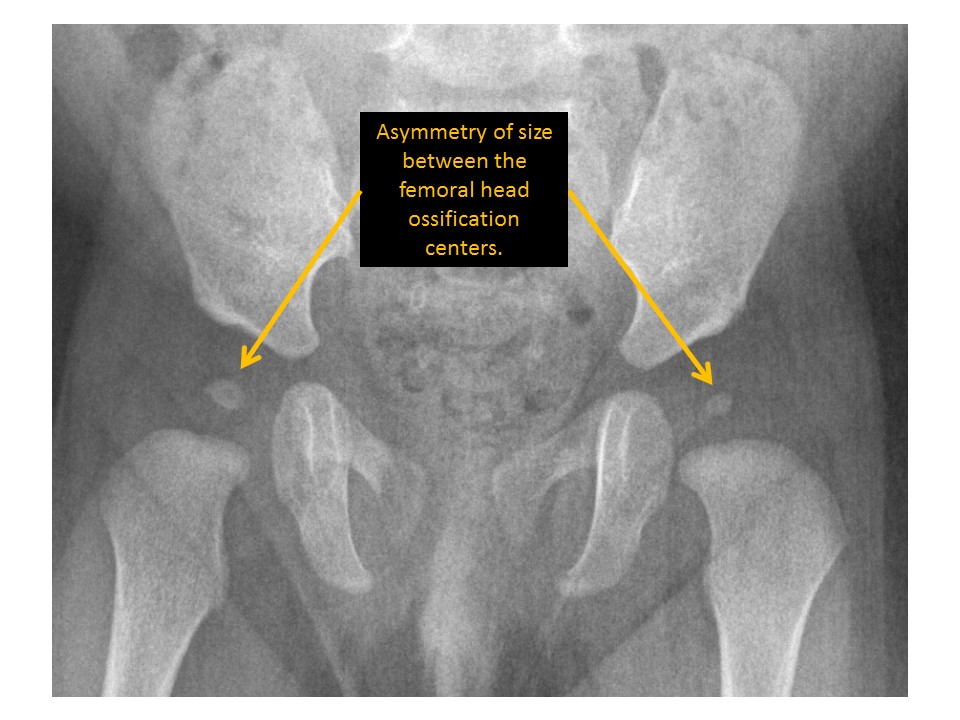

Femoral epiphyseal ossification centers are asymmetric in size. [Yes/No]